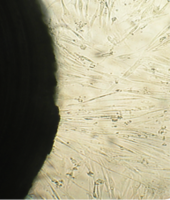

6 серия экспериментов. Образец исследуемого материала (аллогенный ГАП серии «Лиопласт»® массой 2 мг) помещали на дно культуральной чашки, после чего высевали фибробласты в стандартной концентрации.

Щелочной материал резко ухудшает прикрепление фибробластов к дну культуральных чашек (рис. 35) на всей его площади, вместе с тем прикрепившиеся клетки имеют четкие границы, нуклеолемма четко контурирует, цитоплазма гомогенная, без патологической зерностости, вакуолей и включений.

Фибробласты лишь более распластаны по дну чашки, но это характерно для культуры с малой плотностью.

Вокруг образца через сутки от начала эксперимента клетки не прикрепляются (расстояние от края образца до границы 1,3±0,12 мм).

В последующие дни и до конца наблюдения плотность монослоя  в отдаленной от образца зоне нарастает даже несколько быстрее, чем в контроле, клетки сохраняют обычную для фибробластов в культуре морфологию.